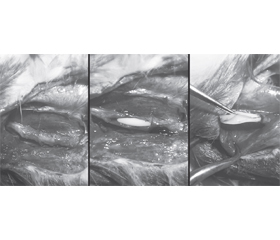

Актуальність. Травми периферичних нервів є надзвичайно актуальною проблемою сьогодення, особливо в умовах воєнного часу. Украй високий відсоток інвалідизації поранених, через що вони не мають змоги повернутися до звичного життя, до 80 % постраждалих є непридатними до подальшої служби. Тому відновлення периферичних нервів є не тільки медичною, але й соціальною проблемою. Мета: дослідження функціонального відновлення сідничного нерва після його тракційної травми, визначення оптимальних стратегій його лікування. Матеріали та методи. Дослідження проводили на 30 безпородних щурах-самцях із середньою вагою 235 ± 55 г, які утримувались у стандартних умовах віварію ДУ «Інститут нейрохірургії ім. акад. А.П. Ромоданова» НАМН України з дотриманням усіх чинних норм біоетики. Щурів утримували за стандартним 12-годинним циклом світло/темрява з наданням вільного доступу до їжі та води. Тварини виводились з експерименту шляхом ін’єкції летальної дози тіопенталу натрію інтраперитонеально. В експерименті моделювали тракційну травму сідничного нерва. Далі тварин розподіляли на три групи залежно від обраного методу подальшого лікування та спостереження. Оцінювання відновлення функції сідничного нерва проводилося із застосуванням комплексного підходу, що включав Walking Track Analysis (тест ходьби по доріжці) з визначенням функціонального індексу сідничного нерва (SFI). Оцінювання проводили на 30-й і 60-й день після операції в І і ІІ групах, а також на 30-й і 60-й день після нанесення тракційної травми в ІІІ групі. Результати. Найгірше відновлення функції сідничного нерва спостерігалося в ІІ групі, тоді як найкращі результати регенерації були зафіксовані в ІІІ групі, у якій хірургічне втручання не виконувалося. При цьому показники груп I і III статистично значущо відрізнялись (p = 0,0027). Високі показники в ІІІ групі можна пояснити природною динамікою відновлення нерва після тракційного ушкодження, що підтверджено електронно-мікроскопічним дослідженням ушкоджених ділянок на 15, 30 і 60-й день після травми. Також слід відзначити низькі показники коефіцієнта варіації, отримані під час аналізу всіх наборів даних, що вказує на високу точність і надійність отриманих результатів. Висновки. Дослідження підтвердило ефективність природної регенерації сідничного нерва після тракційної травми, показавши найкращі результати в групі без хірургічного втручання. Хірургічні методи, такі як накладання епіневральних швів і тубаж із силіконовими імплантами, забезпечували часткове відновлення, проте їх ефективність була обмеженою.

Background. Peripheral nerve injuries are an extremely urgent problem today, especially in wartime. Very high percentage of disabled wounded people does not allow them to return to usual lives; up to 80 % of those injured are unfit for further service. Therefore, the restoration of peripheral nerves is not only a medical but also a social problem. The purpose was to study the functional restoration of the sciatic nerve after its traction injury and to determine the optimal treatment strategies. Materials and methods. The study was conducted on 30 outbred male rats with an average weight of 235 ± 55 g, which were kept in standard conditions of the vivarium of the State Institution “Romodanov Neurosurgery Institute of the National Academy of Medical Sciences of Ukraine” in compliance with all current bioethical standards. Rats were kept under a standard 12-hour light/dark cycle and provided with free access to food and water. The experiment was completed by sacrificing the animals with an intraperitoneal injection of a lethal dose of thiopental sodium. A traction injury to the sciatic nerve was simulated. Then the animals were divided into three groups depending on the chosen method of further treatment and observation. Assessment of restoration of the sciatic nerve function was performed using a comprehensive approach, which included Walking Track Analysis with determination of the sciatic functional index. Assessment was performed on the 30th and 60th day after surgery in groups I and II, as well as on the 30th and 60th day after traction injury in group III. Results. The worst recovery of the sciatic nerve function was observed in group II, while the best regeneration results were recorded in group III, where surgical intervention was not performed. At the same time, the indicators of groups I and III were statistically significantly different (p = 0.0027). High indicators in group III can be explained by the natural dynamics of nerve recovery after traction injury, which is confirmed by electron microscopic studies of damaged areas on the 15th, 30th and 60th day after injury. It should also be noted that the low coefficients of variation were obtained during the analysis of all data sets, which indicates high accuracy and reliability of the results. Conclusions. The study confirmed the effectiveness of natural regeneration of the sciatic nerve after traction injury, showing the best results in the non-surgical group. Surgical methods, such as epineural sutures and silicone tube insertion, provided partial recovery, but their effectiveness was limited.